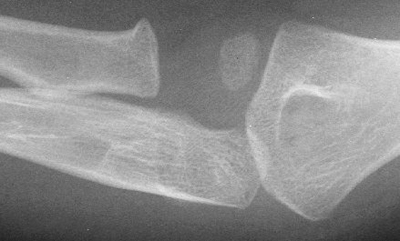

Step 8: Olecranon and ulnar examination

Look for obvious fracture lines and subtle disruptions in cortical contour.

This is not a good lateral radiograph so interpretation of the anterior humeral line is unreliable. There is no obvious anterior or posterior fat pad, and the radio-capitellar line is intact. The radial head and distal humerus appear fine, while there is an obvious proximal olecranon fracture.